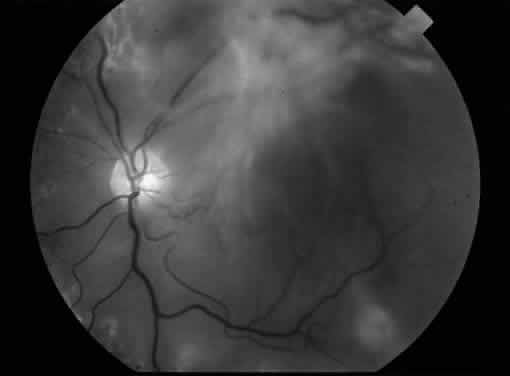

MACULAR TRACTION RETINAL DETACHMENT

Fig. 4. An example of an eye with proliferative diabetic retinopathy and traction retinal detachment involving the macula.